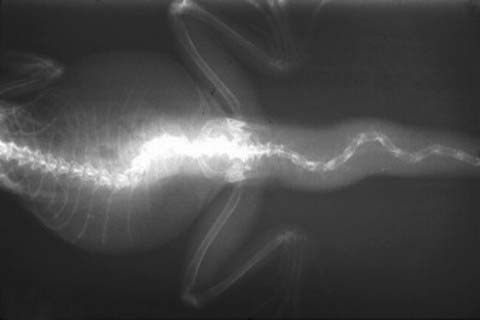

Medical Photos of Iguanas / mbdxray

mbdxray